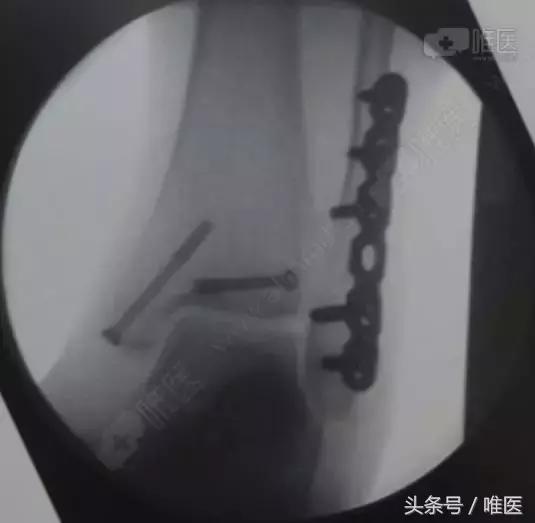

全身麻醉成功后,取左侧卧位,右下肢常规消毒铺巾,右外踝后外侧切口长约8cm切开皮肤、深筋膜,自拇长屈肌及腓骨长短肌间隙进入,暴露外踝及后踝骨折块,复位后踝骨折块后予克氏针临时固定,纠正腓骨远端骨折外移及短缩畸形,克氏针临时固定,透视外踝及后踝骨折复位良好,取合适长度的后侧解剖锁定钢板螺钉牢固固定外踝,空心螺钉固定后踝,再次透视骨折复位及内固定位置良好,冲洗缝合外侧伤口,取仰卧位,右内踝弧形切口切开暴露内踝骨折块及内侧间隙,术中见内踝骨折移位,内侧间隙内碎骨块游离,清理内侧间隙,复位内踝骨折后予导针固定,透视骨折复位及导针位置良好,取34mm长度的4.0 空心螺钉牢固固定,透视骨折复位及内固定位置良好,冲洗伤口,缝合,术中出血约100ml,未予输血。术中伤口予罗哌卡因+得宝松局部镇痛治疗。手术顺利,病人送PACU。

治疗后影像